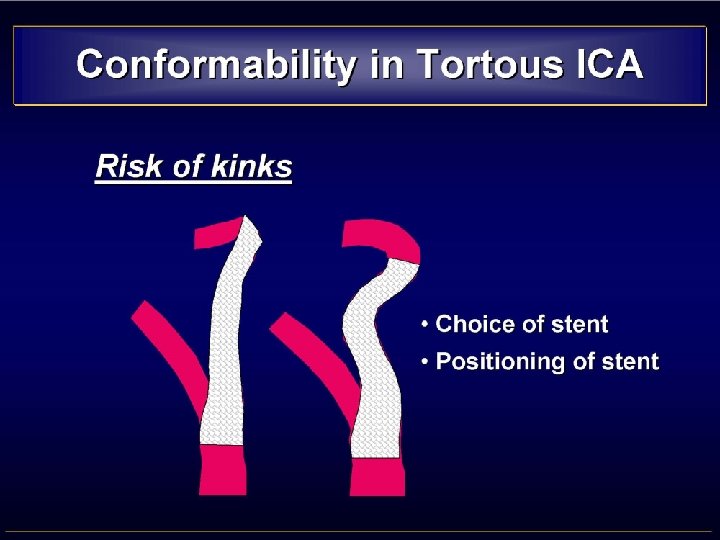

TORTUOUS CAROTID • CONSIDERATIONS - Tend to be straightened out by stents - Resulting in kinking above the stent -A flexible device is mandatory • STENTS REQUIREMENTS - Flexibility - Trackability - Conformability • CHOICE Open-cell design follow the curves better